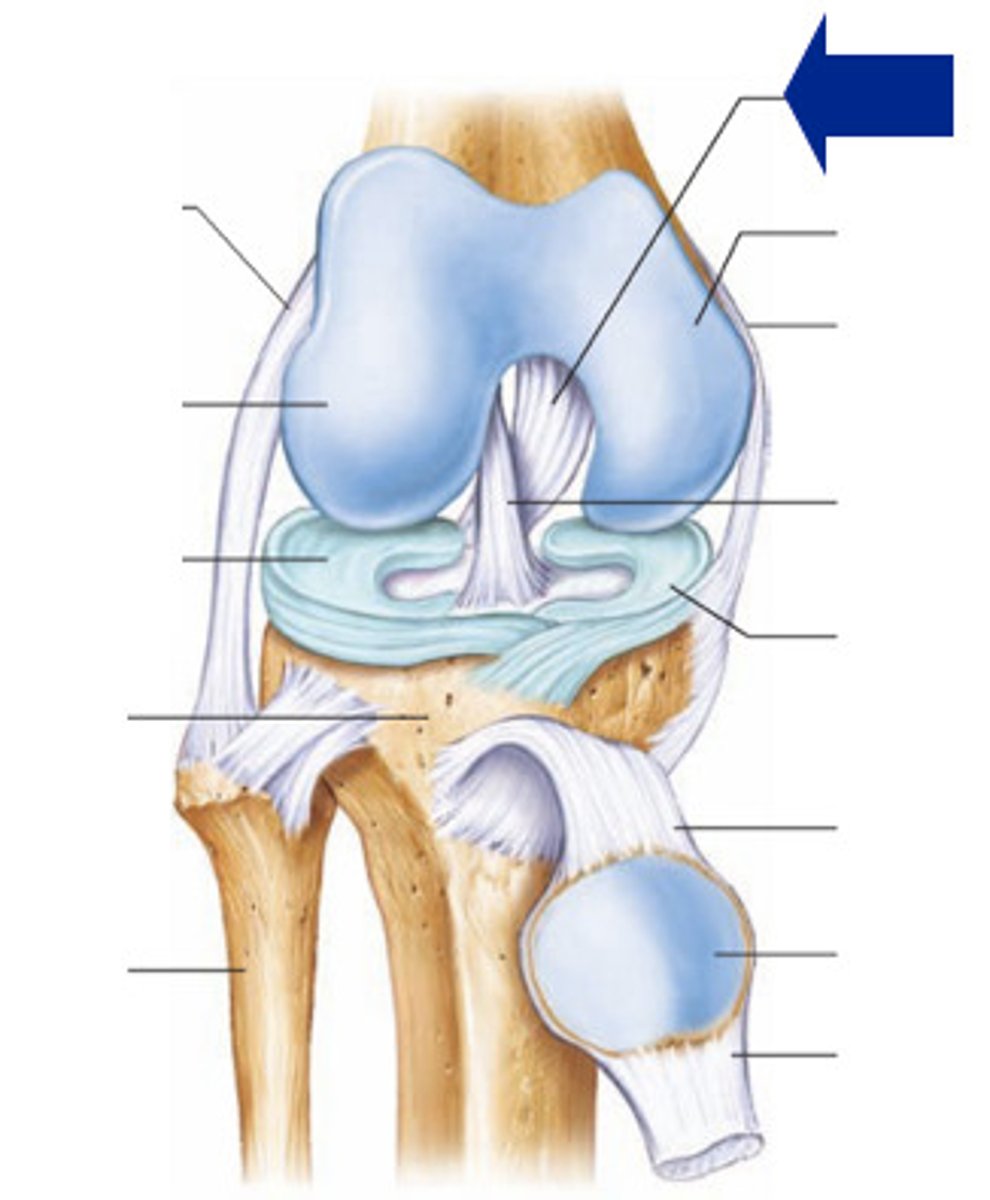

Quadriceps tendon

Patellar ligament

Medial meniscus

Lateral meniscus

Anterior cruciate ligament

Posterior cruciate ligament

Medial (tibial) collateral ligament

Lateral (fibular) collateral ligament